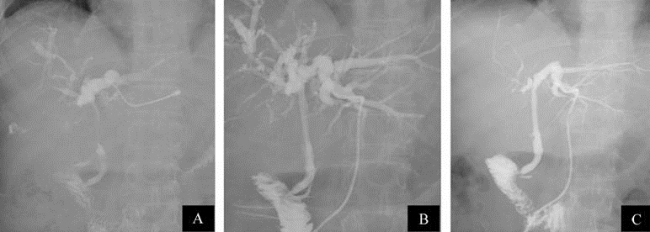

图21-32 经皮肝穿刺胆管引流(PTCD)

A.导丝通过胆管闭塞段;B.球囊扩张;C.置入内引流涵管

图21-33 经皮肝穿刺胆管引流(PTCD)

A.胆管闭塞;B.开通闭塞段;C.置入支架

图21-34 经皮肝穿刺胆管引流(PTCD)

图21-35 经皮肝穿刺胆管引流(PTCD)

A.肝内胆管扩张,肝总管及胆总管上段狭窄呈细线状,胆总管下段正常;B.同时行支架内引流和置管外引流;C.1周后复查,肝内胆管扩张情况已大为改善,外引流置管可拔除